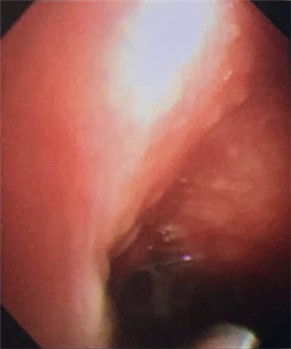

大量藍斑、黏連帶

我院呼吸內科采用改良型“軟式胸腔鏡”,該新設備軟硬結合,前端可彎曲,能多方向觀察胸腔內改變,比老式“硬式胸腔鏡”的探查視野更大,診斷更準確。